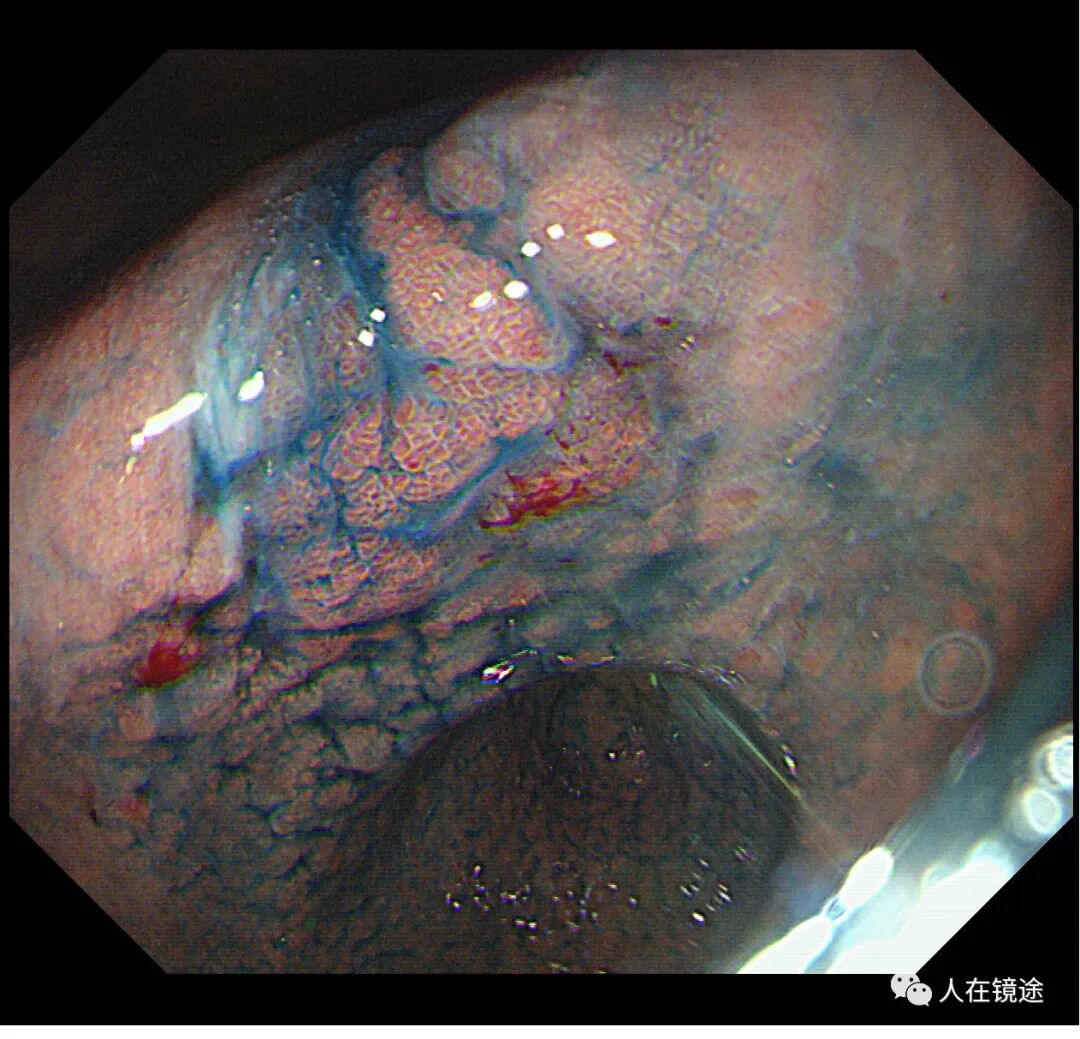

白光示胃窦粘膜红白相间,以白为主,胃窦小弯见一0.8*1.2cmIIa粘膜发红病变,表面粗糙。电子胃镜镜是什么奥林巴斯HQ290电子胃镜诊断胃窦早癌一例分享_https://www.jmylbn.com_新闻资讯_第3张

白光+近焦示:胃窦小弯见一0.8*1.2cmIIa粘膜发红病变,微结构稍紊乱,表面粘膜高低不平伴自发性出血。